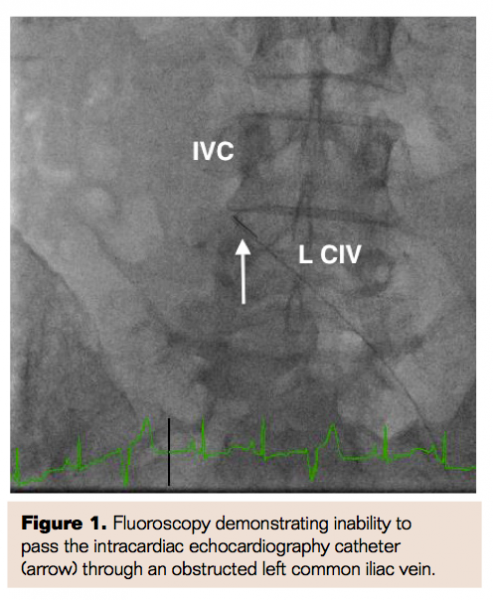

She was brought to the cardiac catheterization lab and prepped in a sterile fashion. Right common femoral vein (CFV) access was obtained and a 12 Fr sheath was placed. Next, access was obtained in the left CFV and an 8 Fr sheath was placed. An Accunav intracardiac echocardiography (ICE) catheter (Siemens) was advanced through the left CFV but was met with significant resistance in the left common iliac vein (CIV) (Figure 1). Selective venogram of the left CIV confirmed a subtotal thrombotic occlusion of the CIV at the inferior vena cava (IVC) junction (Figure 2) consistent with May-Thurner syndrome. A glidewire (Terumo) with a support catheter was advanced to cross the subtotal occlusion into the IVC and a caval venogram was performed to confirm intraluminal position (Figure 3).